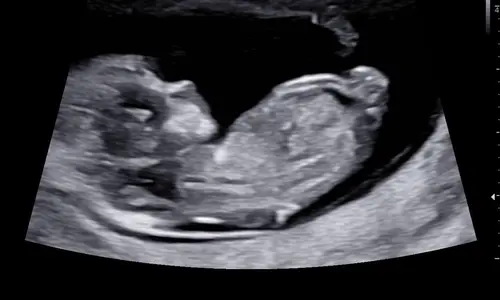

Buiten een erg lief wipneusje is dit een jongetje 馃挋

Aah dat neusje he 馃ス